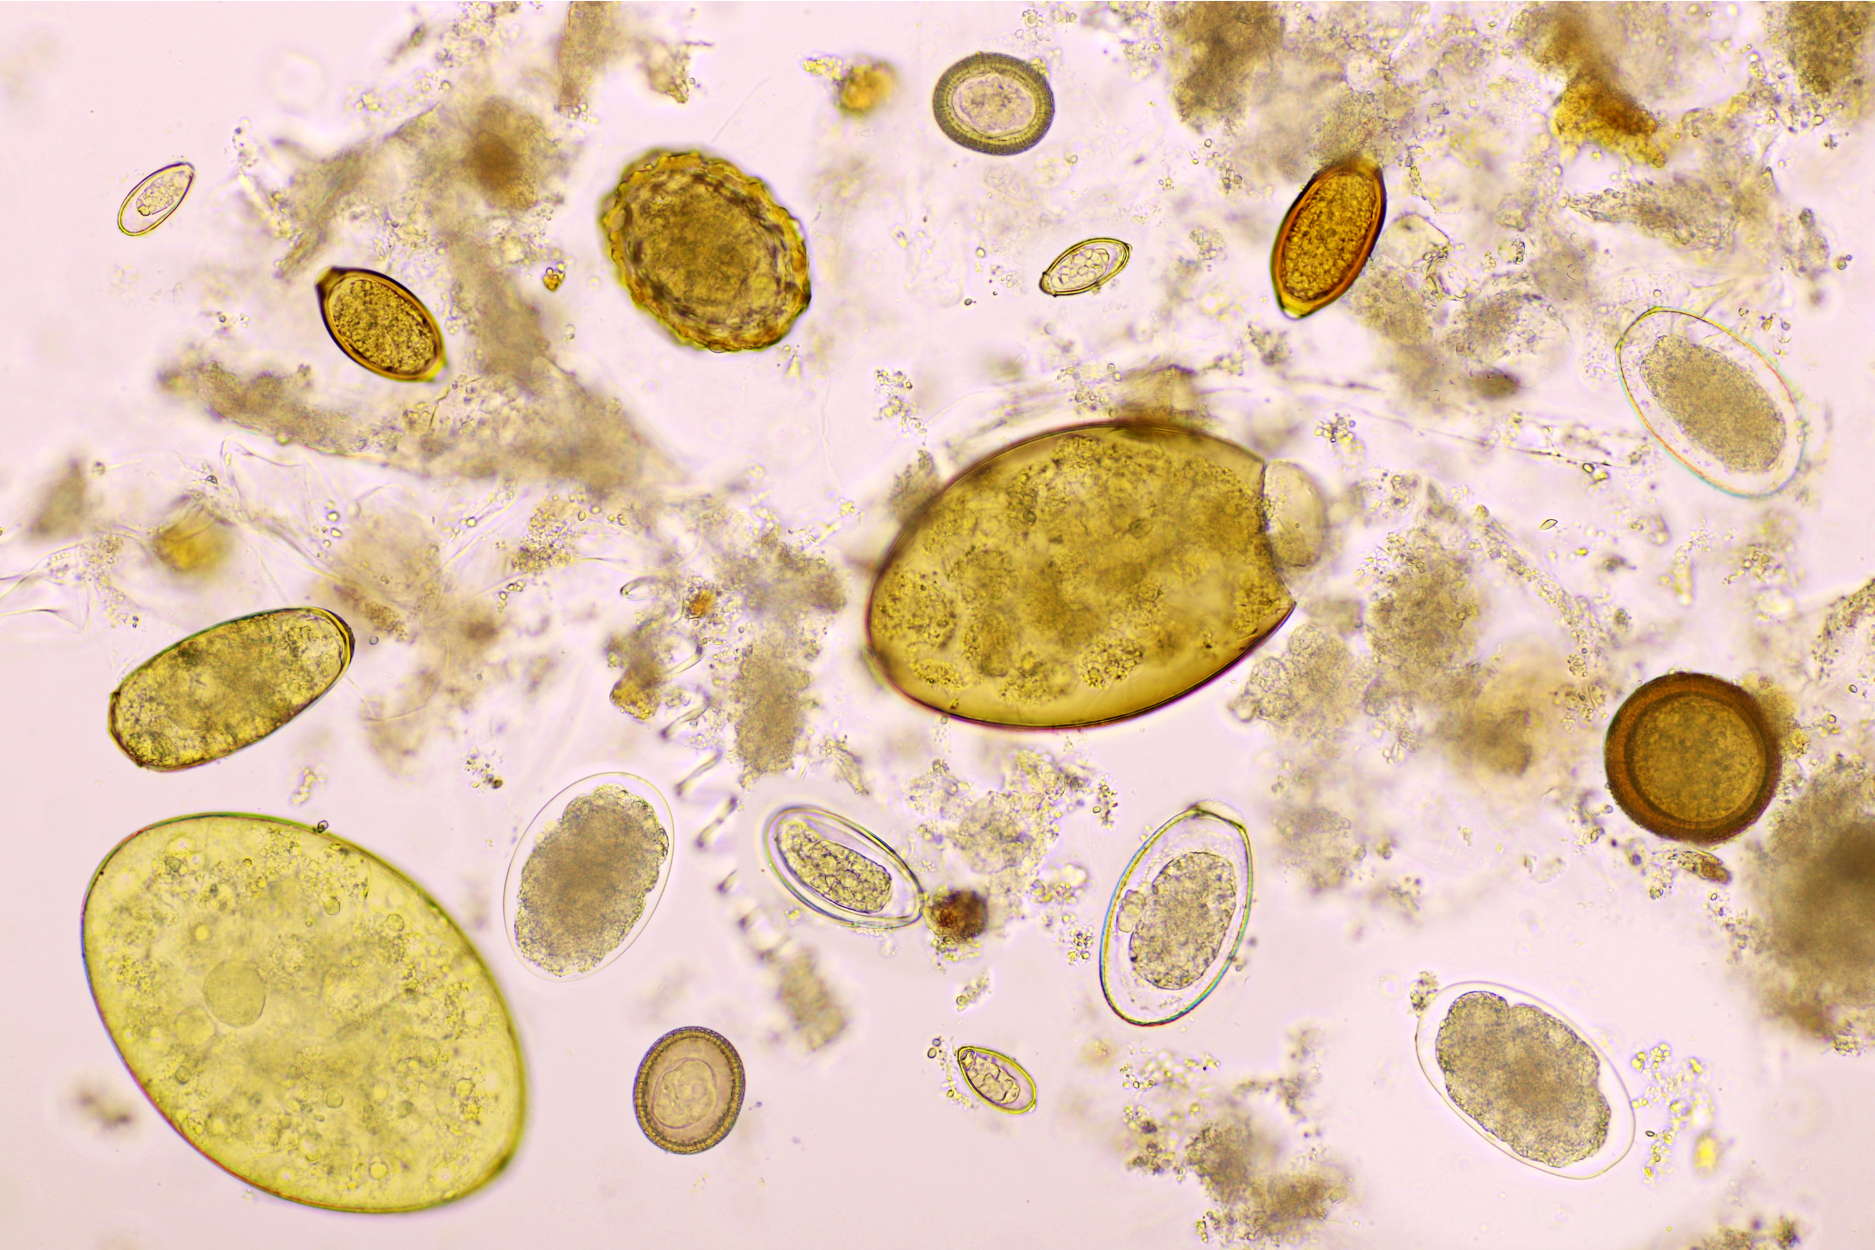

When most people think of parasites, they might imagine external creatures like fleas, ticks, or lice. However, there is an entire world of parasites that live inside the human body, primarily in the intestines. These parasites often consist of protozoa, single-celled organisms, as well as various types of worms, which are multi-cell organisms.

For this article on parasite cleanses, I’ll focus on the most common parasites found in the human intestines.